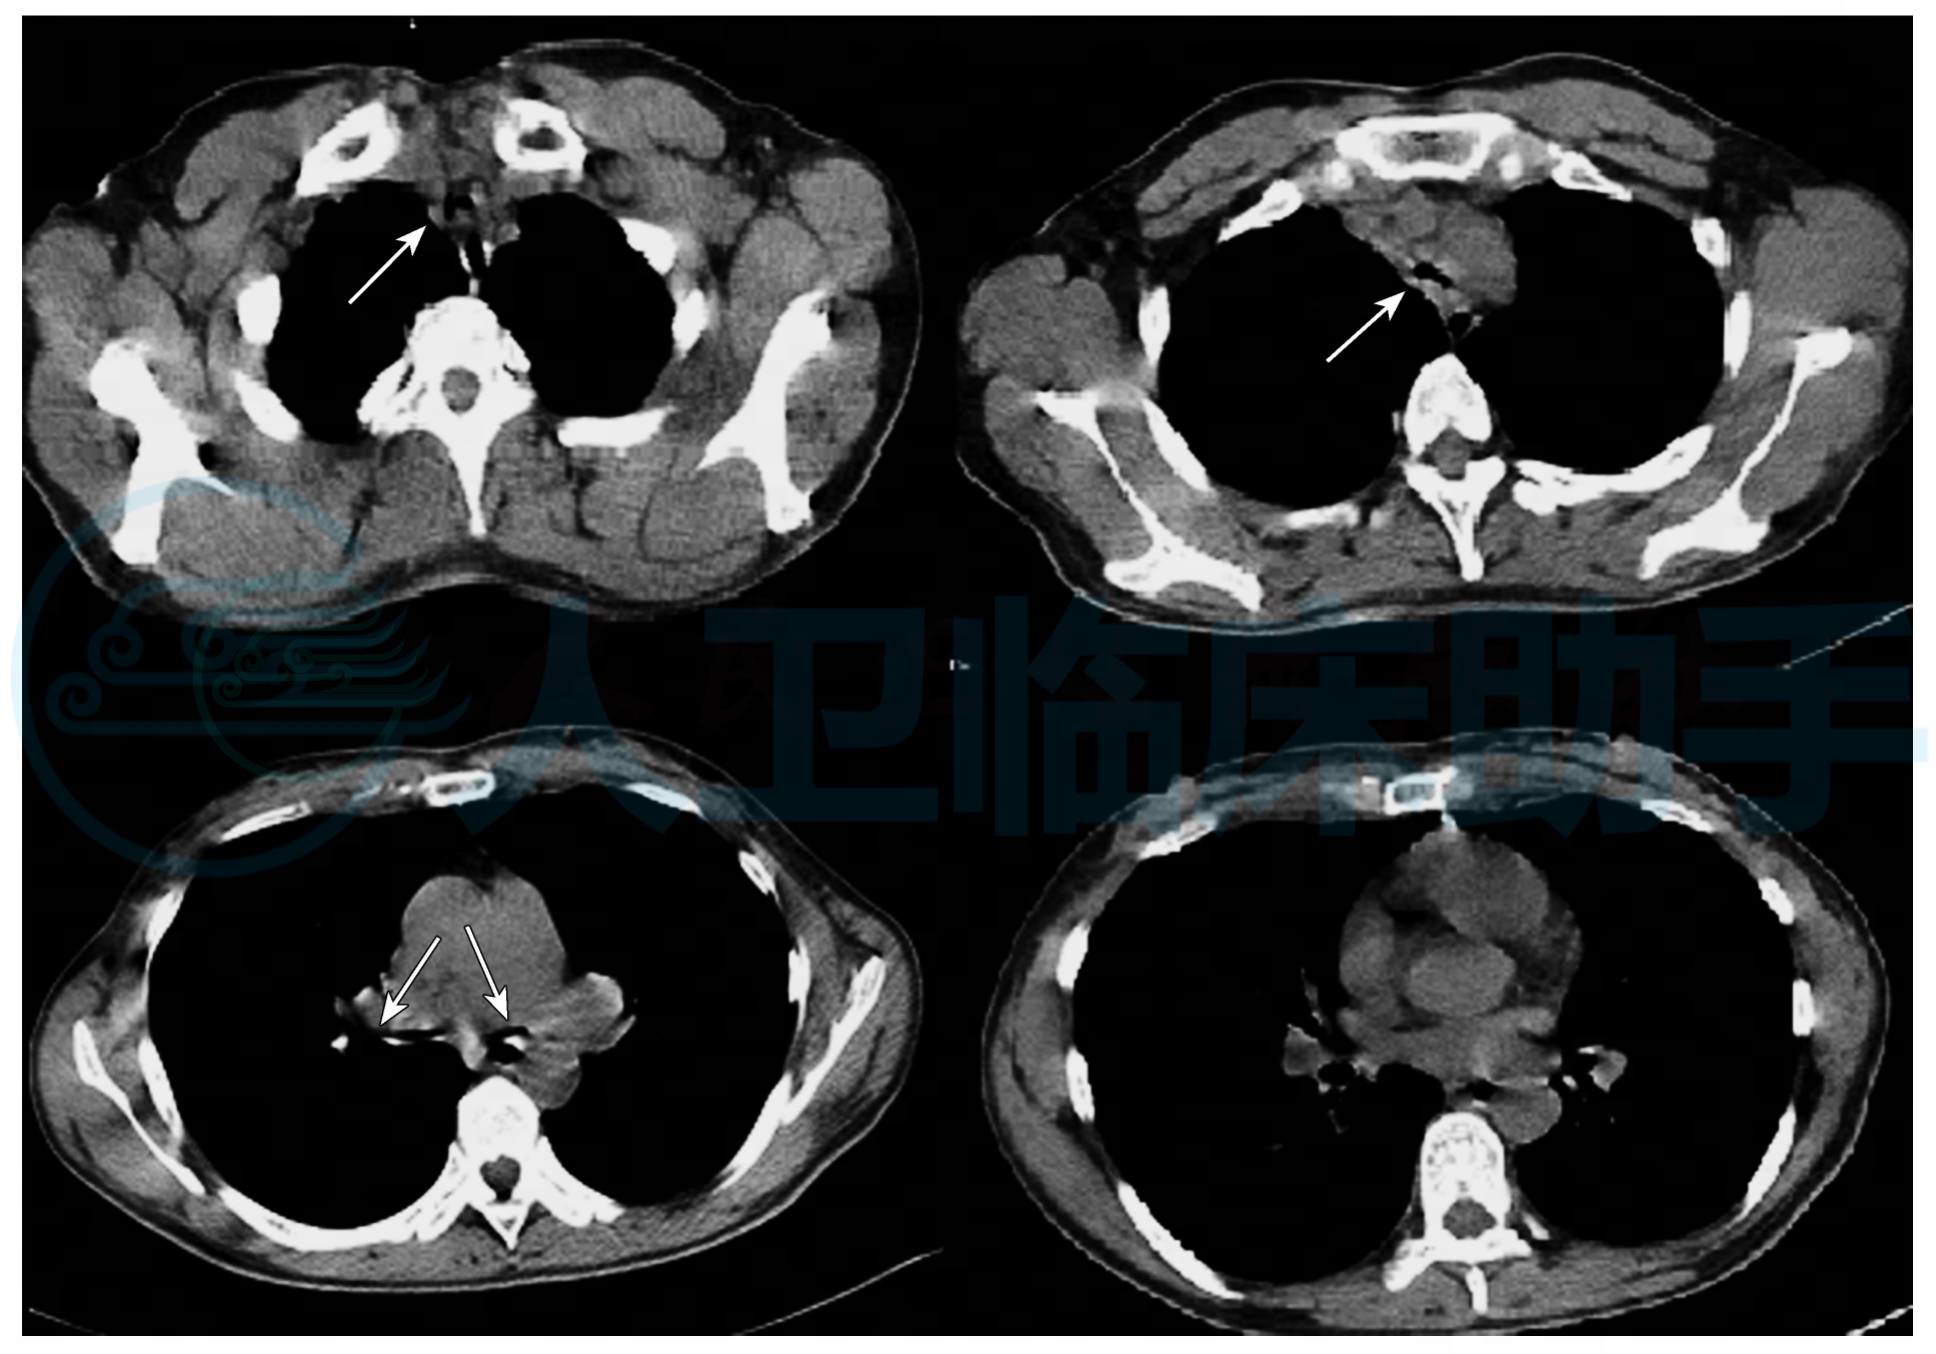

入院辅助检查:血常规:WBC:5.5×109/L,NE%:78.2%,RBC:4.31×1012/L,Hb:95g/L,PLT:627×109/L;CRP 48.10mg/L;肺炎支原体抗体1∶40,军团菌抗体(-)。肺CT检查示左肺门影增大,气管、左右主支气管和左肺上叶支气管广泛狭窄、管壁增厚,气管呈“刀鞘样”变,右肺中叶少量慢性炎症,右锁骨上窝、纵隔内、左肺门多发肿大淋巴结(图1)。

图1 左肺门影增大,气管、左右主支气管和左肺上叶支气管广泛狭窄、管壁增厚,气管呈“刀鞘样”变,其他叶段支气管基本正常,纵隔内、左肺门多发肿大淋巴结